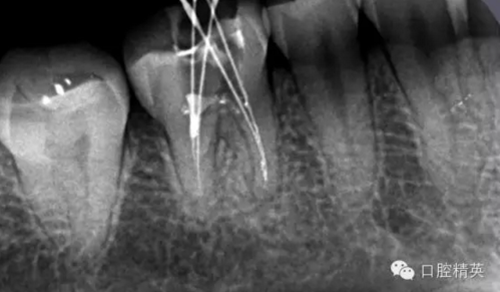

這個(gè)也是我目前接到最有難度的器械分離病例,從片子上看近中器械分離兩節(jié),曾在外院做過干尸,有七年。當(dāng)看到這個(gè)病例時(shí)我沒有多大的把握,因?yàn)槲沂巧硖幓鶎?,無顯微,無放大。我只有抱著試一試的態(tài)度,但是她是我們?cè)簝?nèi)員工,壓力很大。

現(xiàn)在開始看第二張片子我疏通的遠(yuǎn)舌根,有點(diǎn)問題哦!~

根尖孔偏移,或者是片子角度問題,導(dǎo)致我們很難判斷,感覺像是測(cè)穿。但是我們有根測(cè)儀(前提它是好的),因?yàn)楦鶞y(cè)儀是我們目前對(duì)根管測(cè)量最具有說服力,也是最為客觀事實(shí)的。根測(cè)儀沒有顯示一探入根尖下三分之一顯示“over”的情況(我用的是登士博根測(cè)儀)根管內(nèi)無滲出,可以測(cè)出根管的長度。那就證明工作長度的存在,和可信。在看看正題的近中根的器械,我想問問大家覺得是什么器械??